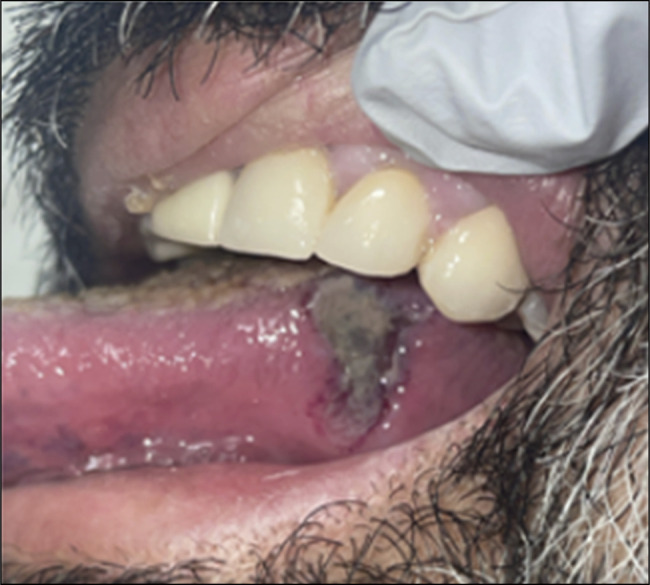

肉芽肿病合并多血管炎(GPA)是一种罕见的小血管炎,通常表现为多器官累及上呼吸道、肺和肾脏。我们报告一位55岁的男性,他表现为口腔溃疡疼痛,弥漫性关节疼痛,鼻出血和间歇性的栗色大便。传染性评价无显著差异。风湿病学评估显示c-抗中性粒细胞细胞质抗体和蛋白酶3抗体升高。结肠镜检查与回肠末端活检显示血管中心炎性发现支持GPA的诊断。本病例的临床表现不同寻常,以口腔表现为主。对于胃肠道出血的患者,GPA的诊断仍然需要鉴别,这些全身性症状需要高度的怀疑才能及时诊断。

Granulomatosis with polyangiitis (GPA) is a rare small vessel vasculitis that commonly presents with multiorgan involvement of the upper airways, lungs, and kidneys. We report a 55 year-old-man who presented with painful oral ulcers, diffuse joint pain, epistaxis, and intermittent maroon bowel movements. Infectious evaluation was unremarkable. Rheumatologic evaluation demonstrated elevated c-anti-neutrophil cytoplasmic antibody and proteinase 3 antibodies. Colonoscopy with terminal ileum biopsies demonstrated angiocentric inflammatory findings supportive of a diagnosis of GPA. This case was unusual in its presentation with predominately oral manifestations. A diagnosis of GPA should remain on the differential for patients with gastrointestinal bleeding, and these systemic symptoms require a high level of suspicion to lead to timely diagnosis.